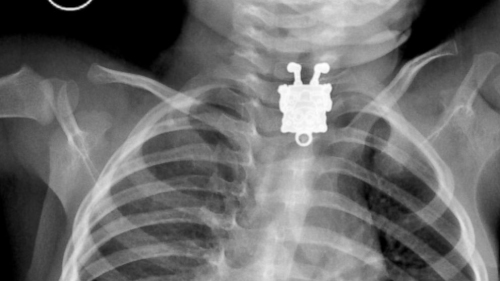

X光片顯示出一個“海綿寶寶”。

中新網(wǎng)1月29日電 據(jù)外媒報道,沙特一名醫(yī)生近日在為一名孩子拍攝X光片時,驚訝地發(fā)現(xiàn)孩子體內(nèi)有一個“海綿寶寶”飾品。

據(jù)報道,這名醫(yī)生叫安吉利,他是阿卜杜拉阿齊茲國王大學醫(yī)院的放射科醫(yī)生。他告訴媒體稱,在X光片里能清晰看到孩子吞下的“海綿寶寶”卡通形象。

安吉利醫(yī)生說,從X光片里看,這個“海綿寶寶”像是一個吊墜,上面有可以掛繩子的地方。

“我覺得也可能是個別針,”安吉利醫(yī)生說,當他第一次看到X光片的時候嚇壞了,一個“海綿寶寶”笑臉相迎的樣子讓他相當震驚,“而且拍攝角度和朝向?qū)嵲谑呛芡昝馈?rdquo;